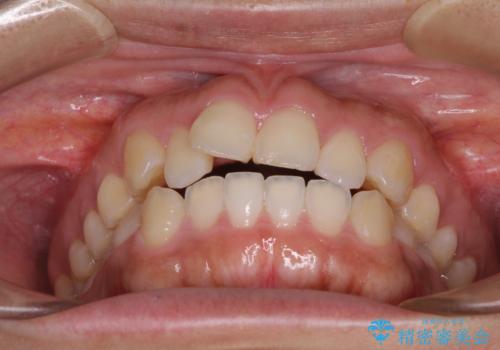

- 口が閉じにくさを気にして来院された患者様です。

上下の前歯が前方に突出していたため、上下左右の第一小臼歯4本を抜歯し、ワイヤー装置にて抜歯矯正を行うこととしました。

上下前歯部の被蓋関係を改善するの時間がかかり、3年間を要することとなりましたが、スッキリとした口元に仕上がりました。